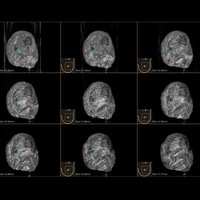

Das IBUS 60 ist ein intelligentes Brust-Vollvolumen-Ultraschallsystem der Marke SIUI.

Das IBUS 60 zeichnet sich durch Sicherheit und Komfort aus. Es bietet ein hochauflösendes Bild und reduziert somit Fehldiagnosen, was ideal für die Brustuntersuchung ist, insbesondere bei einer dichten Brust.

• Dreidimensionale Positionierung